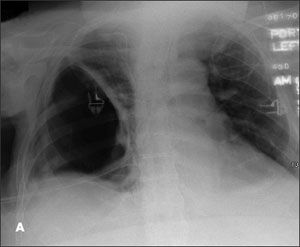

For 3 months, a 63-year-old man had experienced progressively worsening dyspnea. He denied fever, weight loss, and hemoptysis. Eight months earlier, he had had a right thoracotomy to drain a right empyema. Comorbidities included morbid obesity, type 2 diabetes mellitus, hypertension, and obstructive sleep apnea. However, he did not have any intrinsic lung disease.